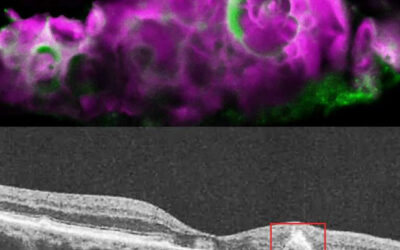

Ensayo clínico para trasplante de EPR en atrofia geográfica asociada con DMAE

Ensayo clínico para trasplante autólogo de epitelio pigmentario de la retina (EPR) con células madre pluripotentes inducidas, para la atrofia geográfica asociada a la degeneración macular relacionada con la edad (DMAE) La degeneración macular asociada con la edad...

Trasplante de células madre: Restaurar la visión en la DMAE puede ser posible

Trasplante de células madre: Restaurar la visión en la DMAE puede ser posible Restaurar la visión en la DMAE puede ser una posibilidad con el trasplante de células madre. Dada la alta incidencia de la degeneración macular relacionada con la edad (DMAE) -con unos 10 u...